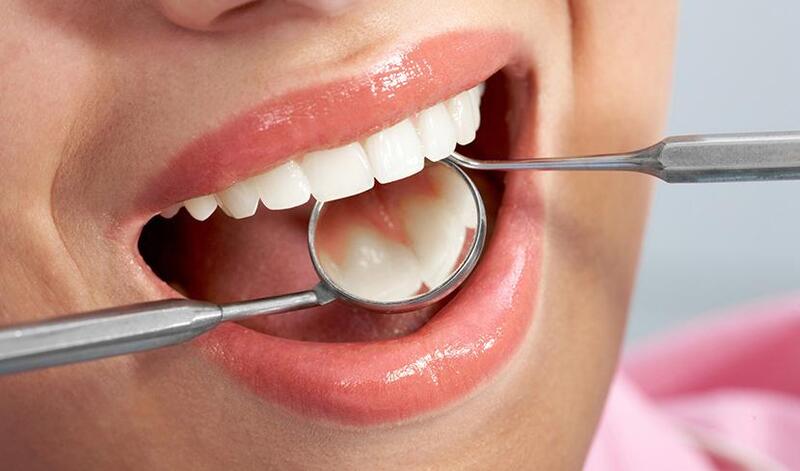

Trám răng thẩm mỹ là một trong những kỹ thuật phục hồi răng được sử dụng phổ biến tại các nha khoa hiện nay. Không chỉ giúp tái tạo hình dạng răng bị sâu, mẻ hay thưa, phương pháp này còn cải thiện thẩm mỹ, mang lại hàm răng đều, đẹp và tự nhiên. Vậy trám răng thẩm mỹ là gì? Khi nào cần thực hiện? Quy trình tại Nha Khoa Hoàn Mỹ Sài Gòn có gì khác biệt? Hãy cùng tìm hiểu chi tiết trong bài viết dưới đây.

Trám răng thẩm mỹ (hay còn gọi là hàn răng) là phương pháp sử dụng vật liệu nha khoa để khôi phục hình dạng, màu sắc và chức năng của răng bị tổn thương như sâu răng, mẻ răng, mòn cổ răng hoặc răng thưa. Điểm nổi bật nhất của trám răng thẩm mỹ là màu sắc vật liệu trùng khớp với răng thật, giúp miếng trám hòa lẫn tự nhiên, khó bị phát hiện.

So với trám răng truyền thống, kỹ thuật trám thẩm mỹ hiện đại mang lại hiệu quả cao hơn về tính thẩm mỹ, an toàn và độ bền.

Quy trình trám răng thẩm mỹ tại nha khoa được thực hiện theo tiêu chuẩn vô khuẩn và kỹ thuật cao, đảm bảo mang lại kết quả bền vững, an toàn và thẩm mỹ tối đa: